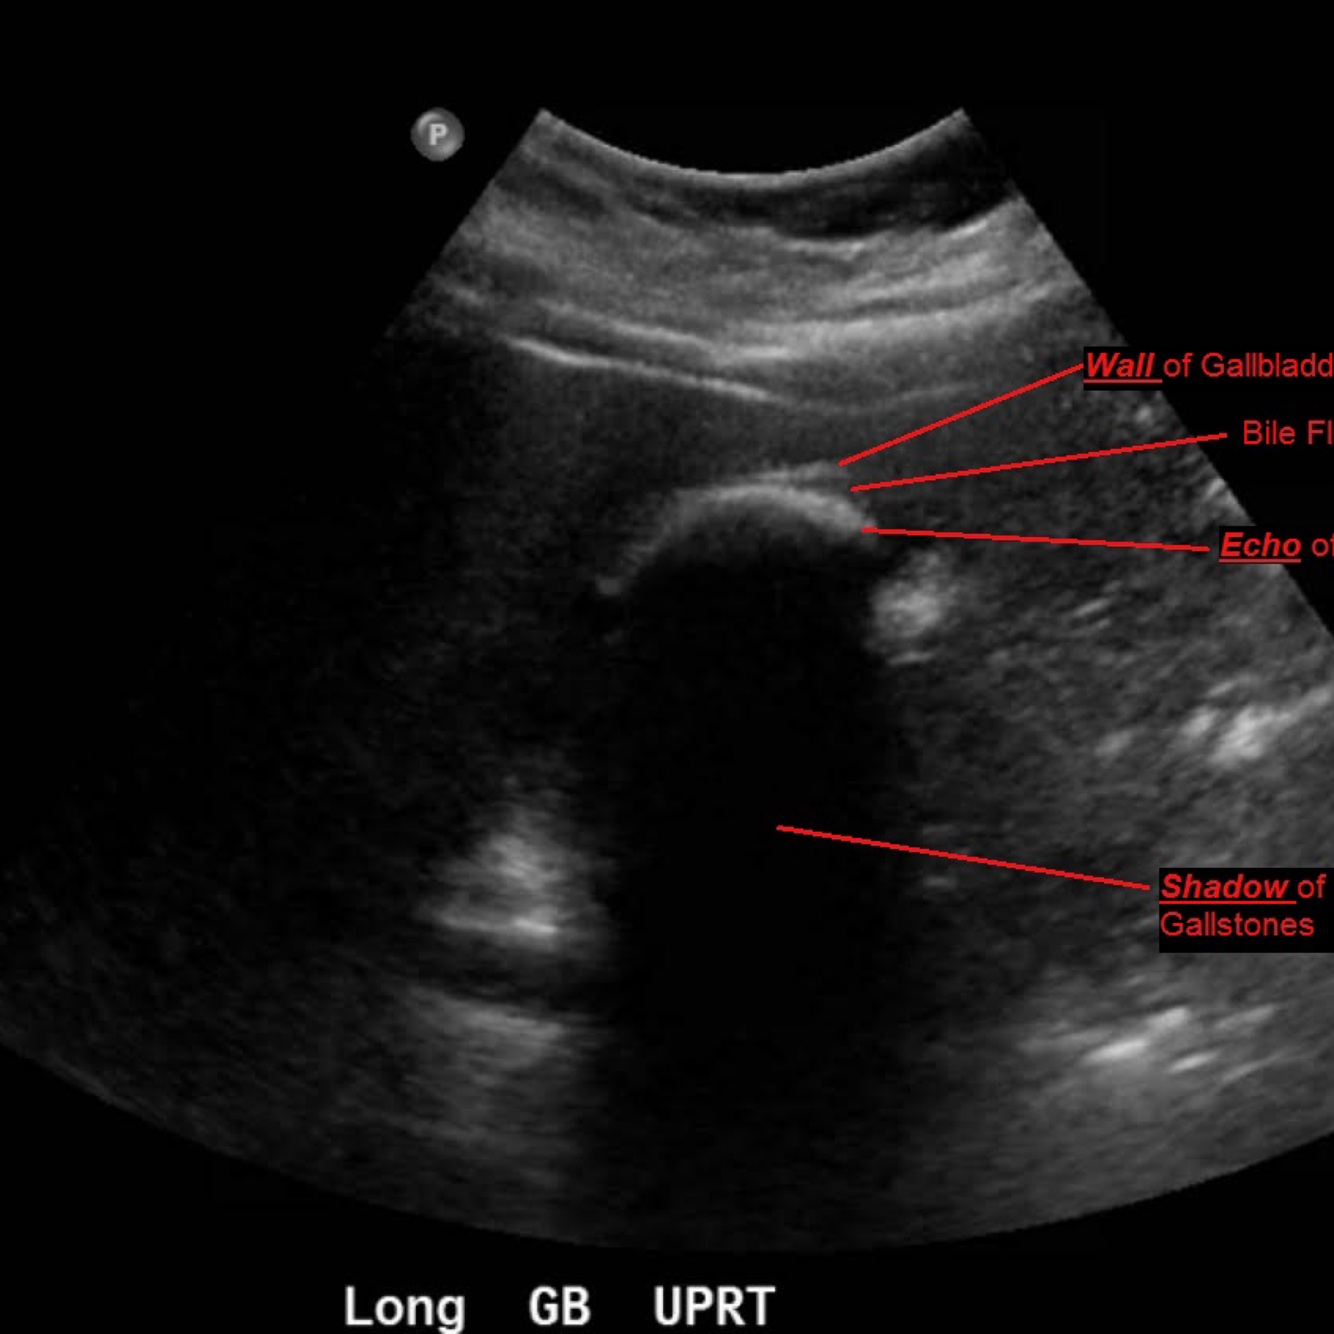

22

Q

A

Wall-Echo-Shadow Triad

●With careful technique, visualize wall–echo–shadow (WES) triad or double-arc shadow sign.

●First arc or curved echogenic line represents thickened GB wall.

●Second arc is from surface of stone followed by posterior acoustic shadowing.

●With chronic disease, GB may be so contracted and is difficult to visualize.

●WES sign can be mimicked by residual barium, a porcelain gallbladder, or Bouveret syndrome.

●Air-filled bowel loops in RUQ may create shadowing which can be mistaken for contracted GB with stones.

●Differential diagnosis for chronic cholecystitis is adenomyomatosis and GB carcinoma.

23

Cholelithiasis: Wall-Echo-Shadow Triad